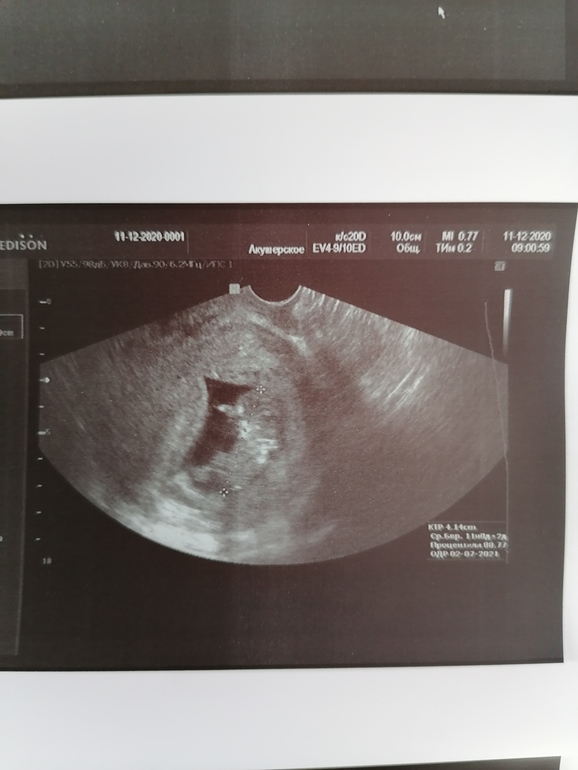

Может кто-то ждёт наше узи🤗.

Ну и по УЗИ все тьфу тьфу тьфу хорошо🙏🙏🙏🥰

КТР аж 41.4, что соответствует 11 неделям, с каждым узи опережение все больше и больше🥰🙏🙏🙏.

Сердечко 162 удара

Ну и вообще колобочек оказался вреднючкой никак не хотел ложится хорошо, махал руками и ногами, но не крутился, но как только врач измеряла мои органы начинал скакать как акробат😂😂😂. Я с боку на бок крутилась и пофигу ему🥰 махал нам с папой ручкой, как-будто говорил, что у него все хорошо и ты мамочка не переживай💙💙💙.

Такой смешной ушастый, носатый и мозговитый это наши выводы после узи😂😂😂. Ушки так смешно торчали🥰🙈.

Половой бугорок не увидела совсем, ноги по турецки лежали 🙈